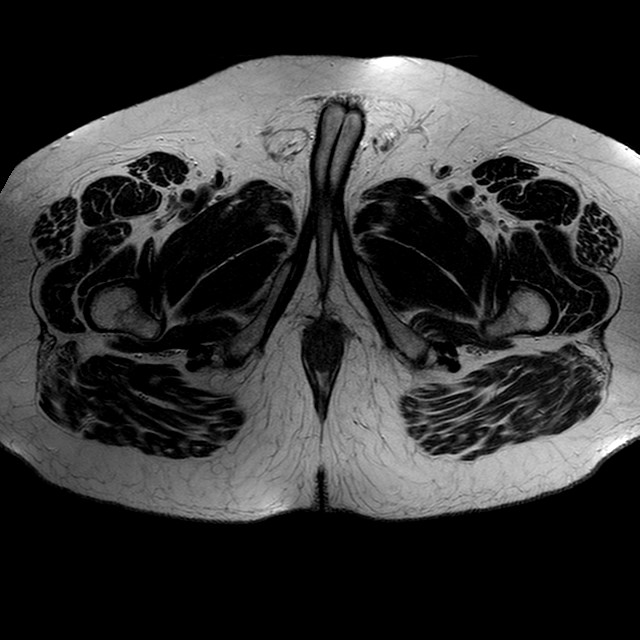

Esami: RMN BACINO

T2w TSE

Evidenti e simmetriche alterazioni osteofitosiche in regione coxo femorale con riduzione delle rime articolari. Degenerazione completa del cercine glenoideo. Non attuali segni di versamento articolare. Non segni di edema osseo che escludono attuale algodistrofia od osteonecrosi. Lieve e simmetrica riduzione del trofismo della muscolatura glutea.